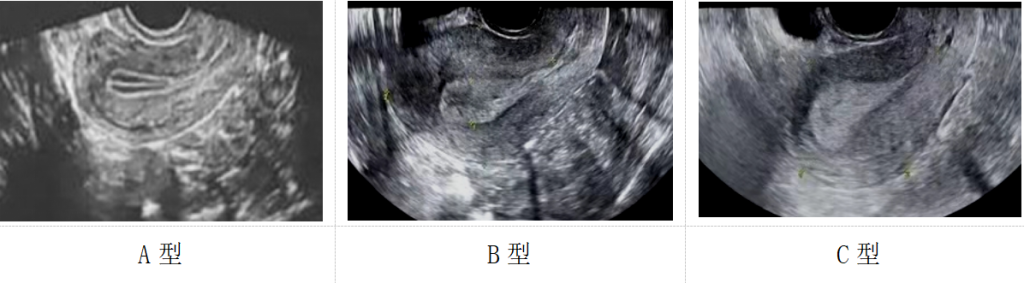

子宫内膜的形态可细分为三线型(A型)、弱三线型(B型)以及均质强回声型(C型)。卵巢与子宫内膜的同步变化,是评估性激素分泌是否正常的重要指标。根据研究,A型和B型子宫内膜的妊娠率显著高于C型,这为临床诊断和治疗提供了重要依据。

子宫内膜的三种形态